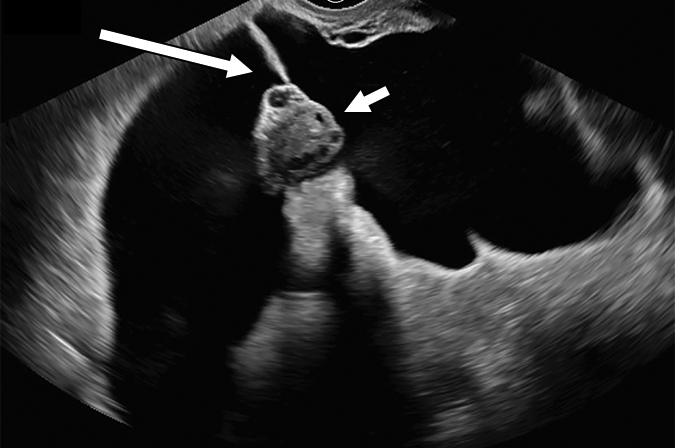

28 岁孕妇,有阑尾切除术史的,在孕早期评估时偶然发现:

超声图像:右侧盆腔积液无占位效应,与邻近盆腔器官相符;悬垂于内的卵巢(短箭头);和代表粘连的分隔(长箭头)。

经典良性病变,腹膜包涵囊肿 (O-RADS 2)。应注意不要将卵巢误认为是固体成分。